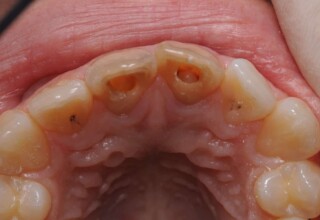

Dark root canal teeth

A rare case of dark root canal teeth with additional external absorption on the central incisor. After removal of the affected tissues of the central incisor, the tooth could not be directly bleached because of the soft tissue contact. The tooth was initially restored to provide the original tooth form, then it was bleached and the restoration was finalized.

Initial appearance